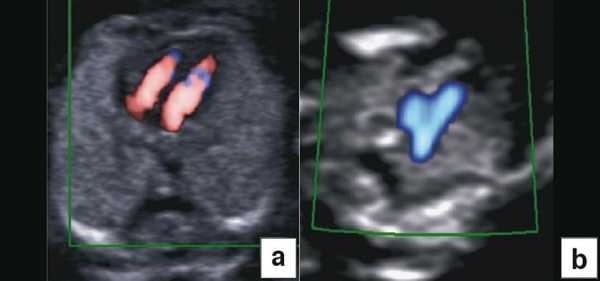

Диагноз хориальности и количества амнионов

УЗИ при двойне в основном должно выявить хориальность (ди- или монохориальность) и для монохориальных беременностей (моно- или диамниотических) - количество амнионов. При многоплодной беременности эта информация необходима для соответствующего ведения дискордантной мальформации, замедления роста, внутриутробной гибели плода или получения образцов ткани плода. Точность этой диагностики в течение I триместра может достигать 100%, а затем на протяжении беременности она уменьшается [7]. Дихориальность подтверждают выявлением лямбда-признака (рис. 4a). Наоборот, монохориальность диагностируют при отсутствии визуализации лямбда-признака или выявлении T-признака (рис. 4b) в межамниотической мембране, расположенной перпендикулярно хорионической пластине.

Рис. 4. Диагностика хориальности и количества амнионов в I триместре путем оценки лямбда-признака (a) и T-признака (b).